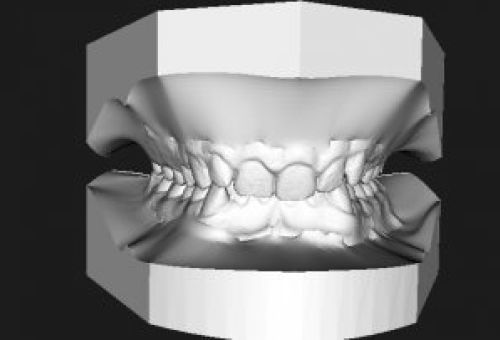

Se trata de un escáner intraoral que obtiene imágenes en tres dimensiones de la mandíbula y cada una de las piezas dentales y huesos.

Permite ver diferentes puntos de vista de una misma pieza dentaria, fundamental para decidir qué tratamiento es el más adecuado.

- Ortodoncia. Se puede ver la evolución que va teniendo el paciente y comprobar que las piezas dentales se sitúan donde corresponde.